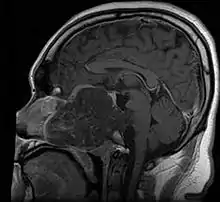

- Skull base:

- May be intracranial or extracranial, with mass effect symptoms depending on location

- Headaches and/or facial pain are common

- Pituitary insufficiency, hemianopsia/diplopia, cranial nerve deficits, nasal stuffiness.